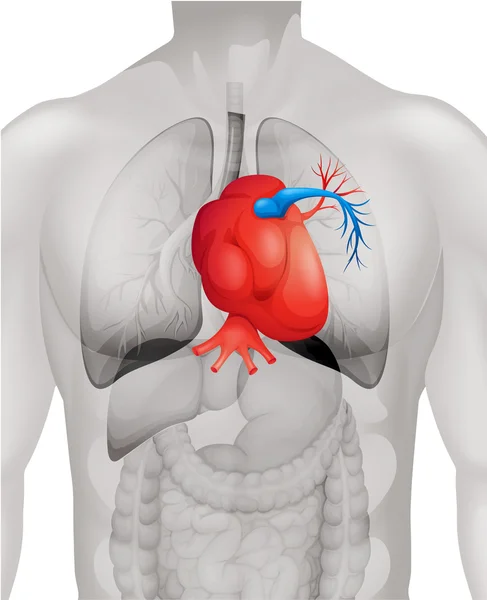

Где находится сердце у человека.

Сердце у человека располагается.

Сердце у человека располагается в грудной полости.

Расположение сердца у человека.

Анатомическое расположение сердца.

Сердце в грудной клетке расположено.

Где расположено сердце у человека анатомия.